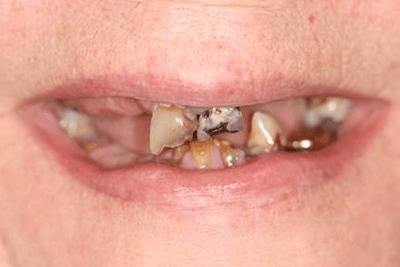

Case 1

Case Details

Here is a picture as the patient presented. We determined together that it was in his best interest to move to an implant retained bar over-denture.